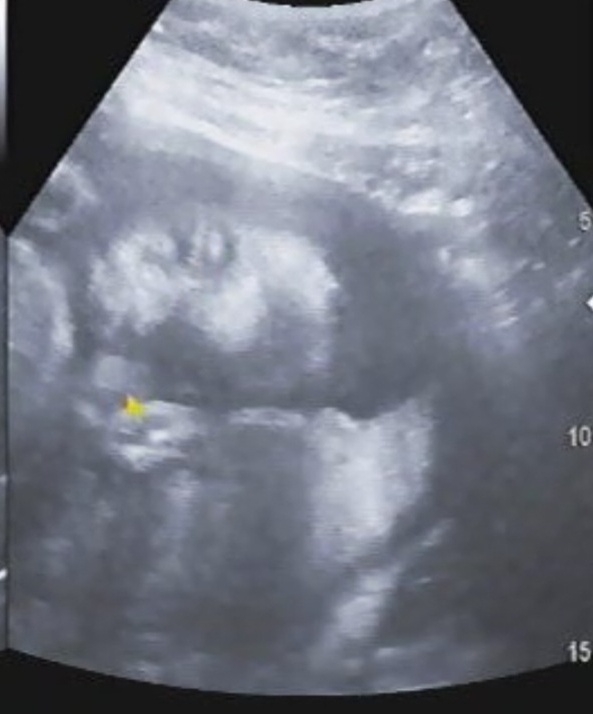

24주 4일차 얼굴 드디어 봤어요

갑작스런 배통증에 병원방문해서 수축검사랑 다 했는데 초음파에서 얼굴을 드디어 보여쥬네요!!